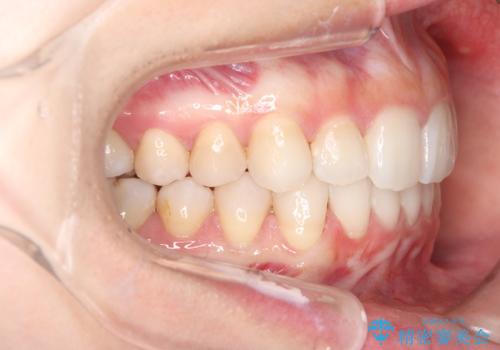

- 前歯のデコボコ(叢生)と、前歯が上下逆の咬み合わせ(反対咬合)を主訴にご来院されました。精密検査の結果、歯列全体のスペースが不足していることが判明。患者様のご希望に合わせ、透明で目立ちにくい**インビザライン(マウスピース矯正)**による治療計画を立案しました。歯を抜かずに、歯列全体を奥(遠心)へ移動させることで、歯が並ぶスペースを確保し、叢生と反対咬合を同時に改善することを目指します。

今回の矯正治療では、透明なマウスピース型の装置インビザラインを使用しました。この装置は目立たず、取り外しが可能なため、食事や歯磨きも普段通り行えます。治療は、緻密な治療計画に基づき、段階的に作製されたマウスピースを交換していくことで、遠心移動という方法で奥歯から徐々に歯列全体を後方へ動かしました。これにより、不足していたスペースを確保し、前歯のデコボコを解消。同時に、上下の歯の前後的な関係を改善することで、反対咬合も正常な咬み合わせへと導きました。見た目も機能も改善し、自然で美しい笑顔を獲得していただけました。